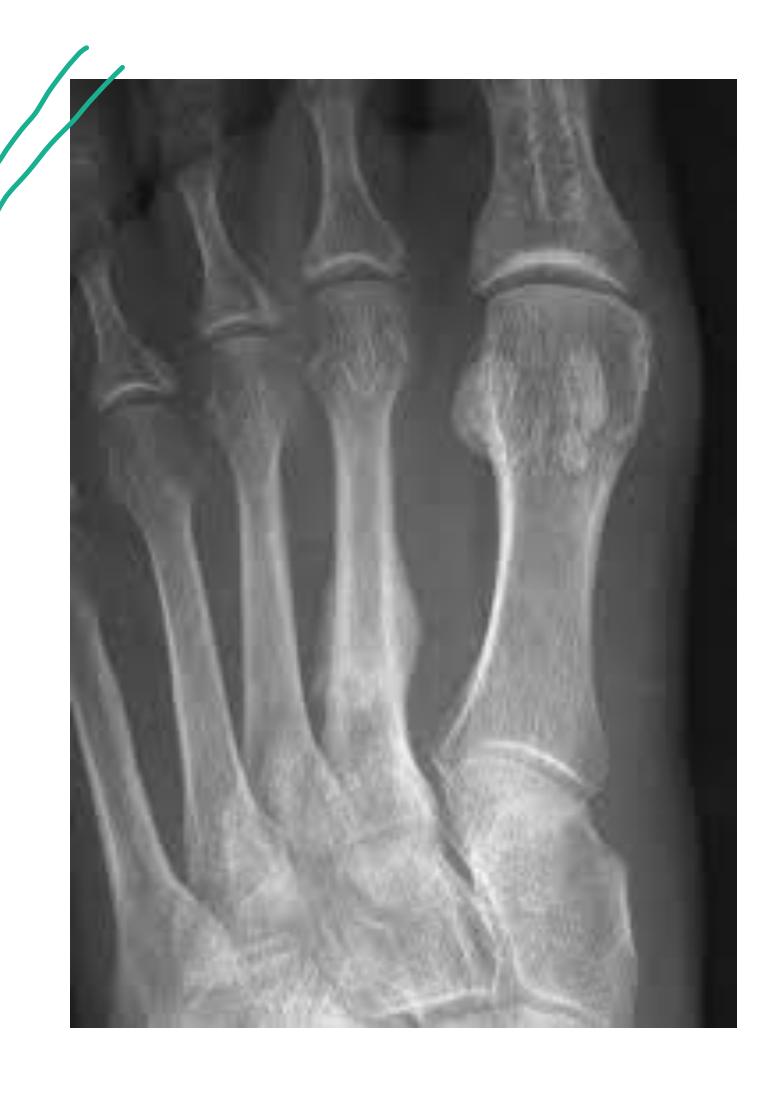

A teenager with acute onset of pain in the right hip during a run. He sustained the injury seen in the x-rays with a white arrow. This injury usually occurs due to a forceful eccentric contraction of which of the following muscles?

- C. Rectus femoris

- Sartorius

Which of the following muscles is attached to the structure pointed by the arrow?

- C. Sartorius

Note: Arrow was pointing at ASIS (Anterior Superior Iliac Spine)